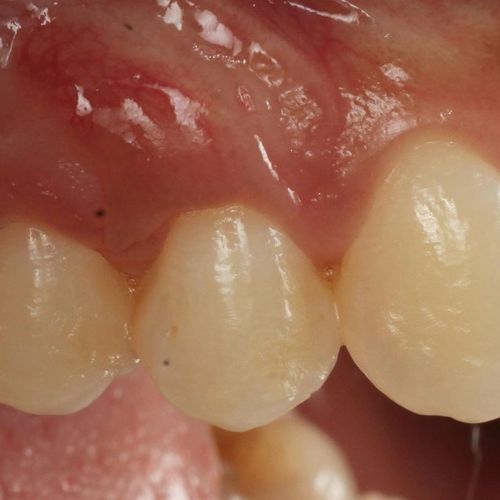

Before and after Periodontal Therapy

![]() | ![]() |

| Untreated severe gum disease | Gum disease treated and stabilised by Dr Halai |